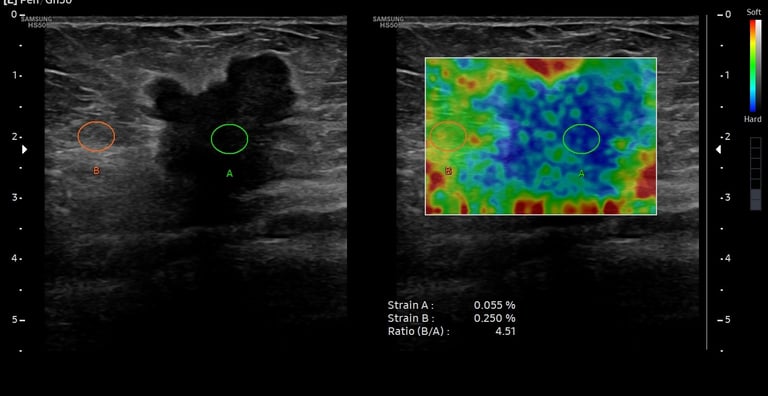

Nodul tiroidian - aspect ecografic sugestiv pentru malignitate - elastografia întărește suspiciunea

BIRADS 5 - tumoră mamară malignă - ecografic hipoecogenă, margini neregulate, halou hiperecogen, rigiditate crescută și SR crescut la elastografie